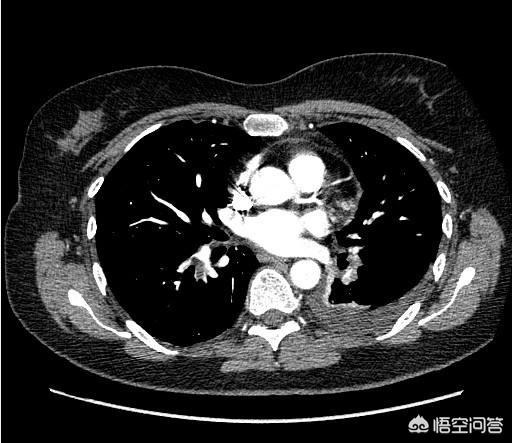

1) Scanner de l'ensemble de l'abdomen + tomodensitométrie améliorée

De nombreuses personnes ne savent pas que le scanner abdominal est également divisé en deux catégories : simple et amélioré. Quelle est la différence ? Un scanner de l'abdomen entier est bon marché : quelques centaines de dollars pour une vue d'ensemble. Pour plus de détails, vous devez opter pour une tomodensitométrie de contraste et de rehaussement, c'est-à-dire un médicament injecté dans les vaisseaux sanguins pendant l'examen, de sorte que les vaisseaux artériels et veineux sont visualisés dans l'image tomodensitométrique rehaussée. Comme tous les organes abdominaux sont irrigués par des vaisseaux sanguins, chaque organe peut être vu plus clairement qu'avec un scanner simple, qui est également beaucoup plus coûteux.

Par exemple, je reçois un patient en consultation externe. Le patient passe d'abord une échographie qui révèle une masse sur le foie qui ne peut être caractérisée. À ce stade, si l'on ne fait qu'un simple scanner, il ne sera peut-être pas possible d'aller déterminer la nature de la masse. Avec un scanner + rehaussement, je peux observer l'aspect de la masse sur le scanner sans contraste. Avec contraste, je peux observer l'aspect de la masse lorsque les vaisseaux sanguins du foie sont remplis de produit de contraste. Sur la base des caractéristiques d'imagerie du cancer du foie, je peux ensuite déterminer si la masse est un cancer du foie.

En combinant la tomodensitométrie simple et la tomodensitométrie améliorée, les tumeurs de l'abdomen peuvent être visualisées de manière dynamique. Les organes de l'abdomen sont divisés en organes pleins et organes creux, et le scanner est plus performant pour les organes pleins de l'estomac (par exemple le foie, le pancréas, la rate, etc.) et moins performant pour les organes creux (tractus gastro-intestinal, uretères, etc.). C'est pourquoi deux autres examens doivent être ajoutés : la gastroscopie et la coloscopie.